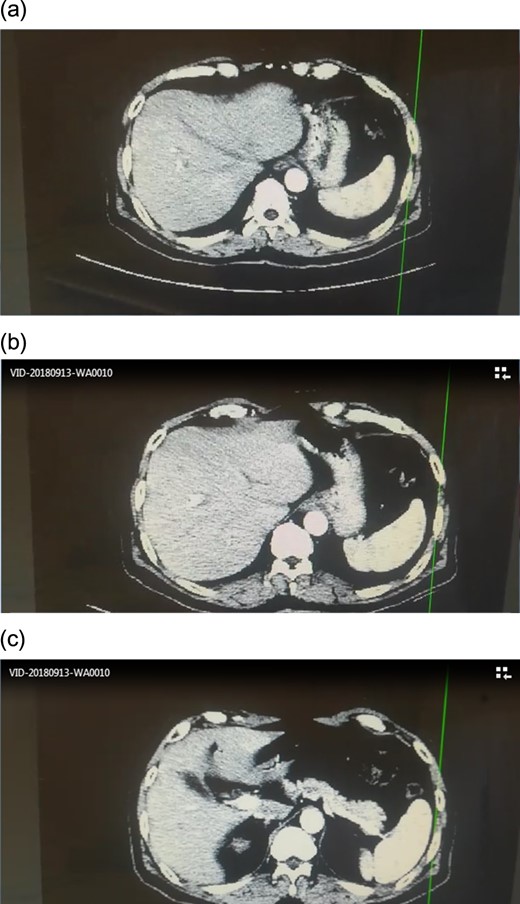

CT scan showed no signs of metastasis (Fig. 1).